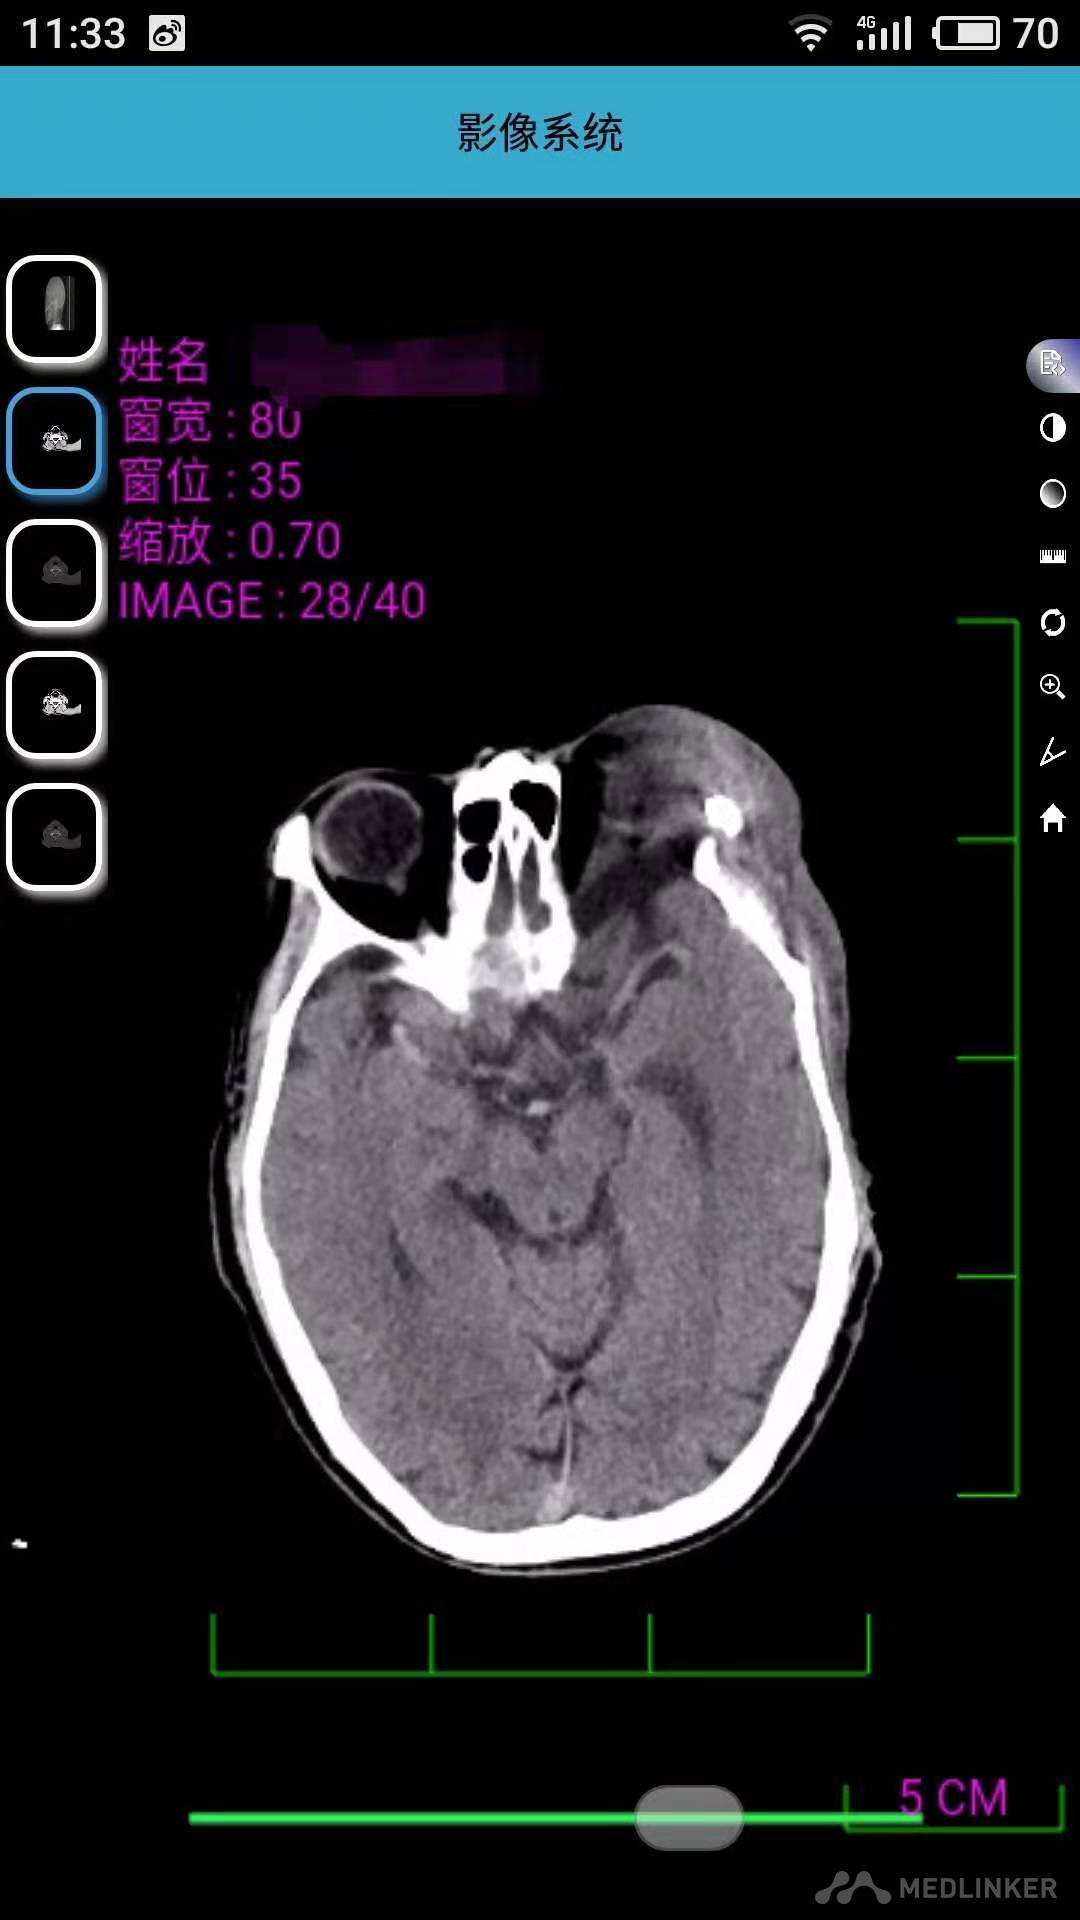

面部左右不对称,比例不协调,左侧上睑下垂,眼球动度异常,对光反射及调节反射不灵敏,左侧面部大面积棕色斑,左侧面部15cm*10cm肿物,边界清,活动度可,质地软,皮温正常,触痛阴性,胸部、腹部及背部多发散在肿物凸起。具体见图。CT示左侧颞骨及眶外侧壁局部骨质不连续,左侧颞极蛛网膜间隙增宽并部分突入颞部肌间隙内,左眼受压旋转。